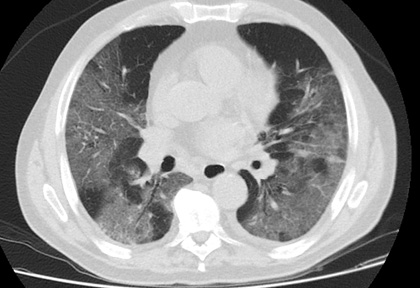

Routine clinical laboratory assays were performed in the hospital’s clinical laboratories. Clinical and laboratory information was extracted from the patients’ medical records. C reactive protein (CRP) in plasma was measured by immunoturbidimetry (Beckman Coulter, Krefeld, Germany). Interleukin-6 (IL-6) levels in plasma were measured by electrochemiluminescence (Siemens Medical Solutions Diagnostics, Siemens Healthcare, Erlangen, Germany). CT scans were read by experienced radiologists who scored results by severity using the criteria shown in Figure 1.

Figure 1. Clinical assessment of pneumonia severity based on computed tomography (CT) scores.

Scoring method: Mild (CT-1)—no more than three ground-glass opacities of <3 cm maximum diameter. Moderate (CT-2)—more than three ground-glass opacities; less than 50% involvement by visual assessment. Medium-heavy (CT-3)—ground-glass opacities and pulmonary consolidation; 50-70% involvement by visual assessment. Severe (CT-4)—diffuse ground-glass opacities with or without consolidation; more than 75% involvement by visual assessment.